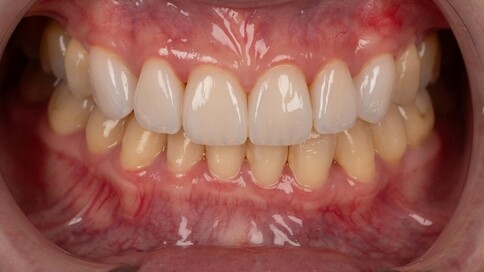

✨ 四、 陶瓷貼片:美學微整

Case 9:氧化鋯貼片改善四環黴素變色。

Case 10:改善不均勻齒色,修復磨耗邊緣。

Case 11:Amber Mill 琥珀瓷造就自然透亮笑容。

Case 12:貼片延伸至牙縫,降低病變並修補空隙。